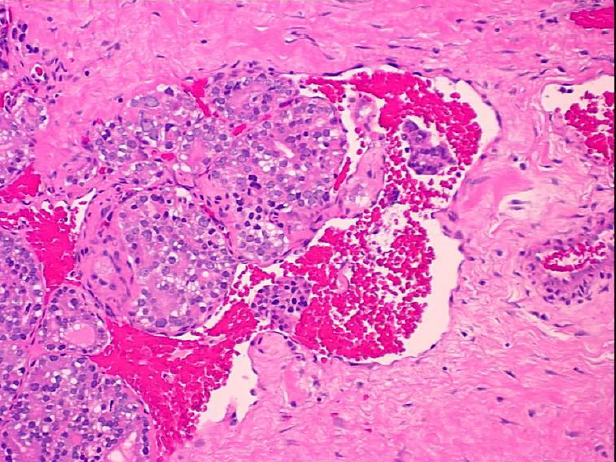

Papillary CA Histology

What are the most important features?